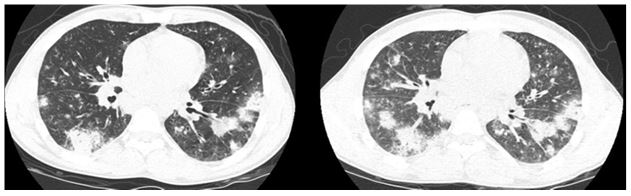

High resolution CT of the chest: (representative image shown; inspiratory (left) expiratory (right))